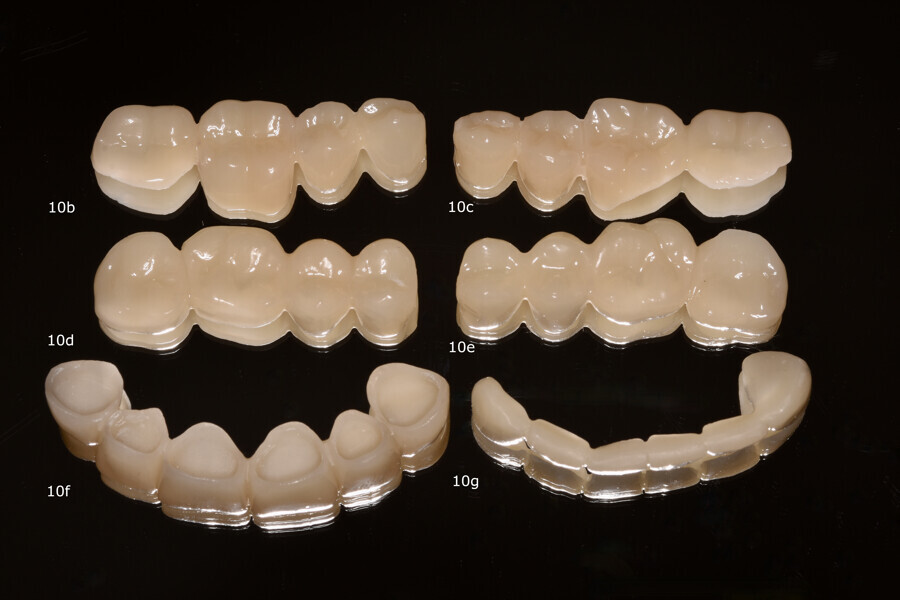

Fig. 8: Provisional restorations in the CAM software with supporting structures.

The scan data of the upper and lower jaw was digitally matched with the digital scan of the initial situation by means of anatomical reference points in the exocad software. The maxillomandibular relationship initially determined for the fabrication of the splint could thus be adopted, and the digital design of the restorations could be carried out. For stability, the provisional restorations in the anterior and posterior regions were designed as contiguous segments in this case. The STL data set of the restorations was then transferred to the CAM software Netfabb 2022.0 (Autodesk), and supporting structures were added to the non-functional areas (Fig. 8). The long-term provisional restorations were printed from V-Print c&b temp (Fig. 9).

After a dripping time of 10 minutes, unpolymerised resin residue was removed from the printed objects using a brush soaked in isopropanol. The objects were then detached from the build plate, and the supporting structures were removed. Post-polymerisation was performed 15 minutes after the last isopropanol contact, using two cycles of 2,000 flashes each in the Otoflash G171 (NK Optik). After post-processing, the provisional restorations were finished and polished to a high gloss (Figs. 10a-g). Finally, the temporary luting was completed with a dual-polymerising temporary luting composite (Bifix Temp, VOCO; Figs. 11a-e).